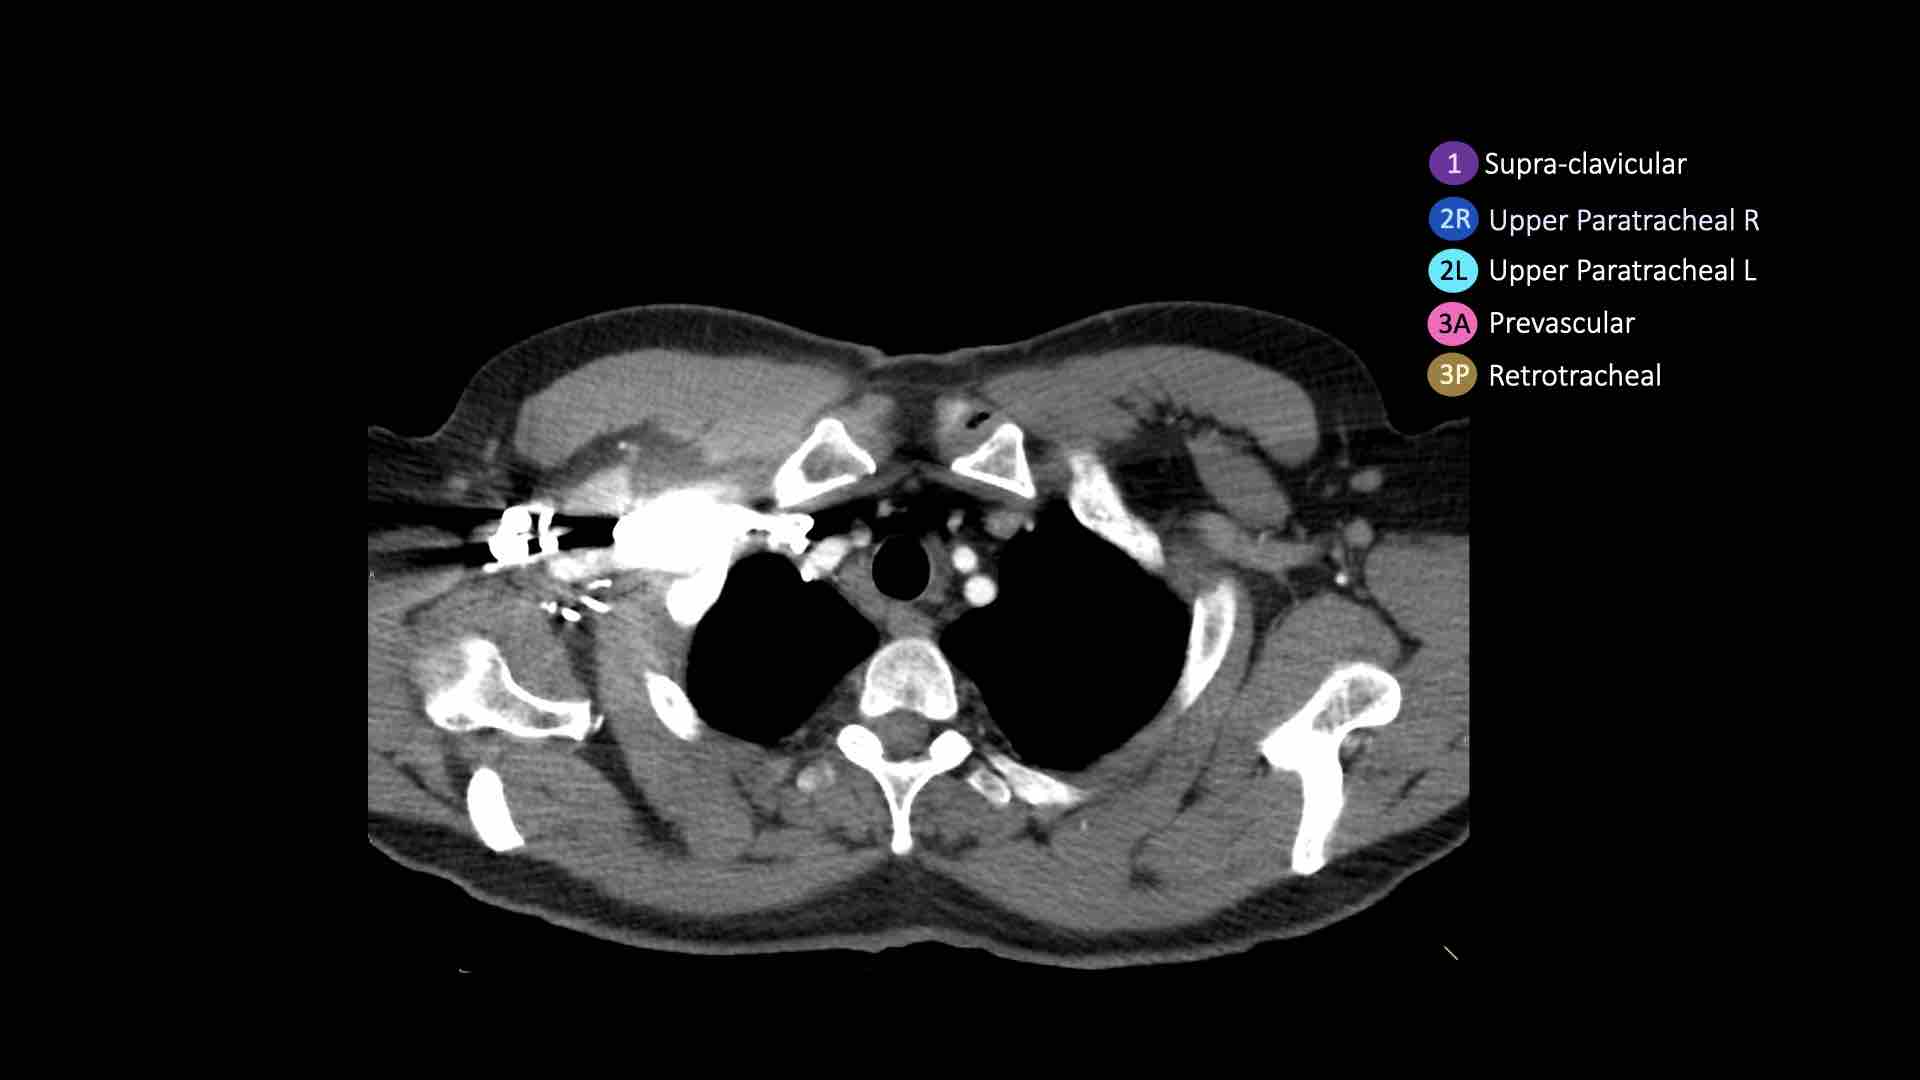

Giải phẫu CT cắt ngang

Nhấp vào hình ảnh để phóng to.

Sau đó cuộn qua các ảnh CT cắt ngang.

Hình ảnh do Bác sĩ Aurelia Fairise thuộc Viện Ung thư Lorraine tại Nancy cung cấp.

3. Hạch trước mạch máu và trước cột sống

Hạch nhóm 3 không nằm kề khí quản như hạch nhóm 2.

Chúng có thể là:

3A nằm phía trước các mạch máu, hoặc

3B nằm phía sau thực quản, vốn nằm ở vị trí trước cột sống.

Hạch nhóm 3 không thể tiếp cận bằng nội soi trung thất.

Hạch 3P có thể tiếp cận bằng siêu âm nội soi (EUS).

Bên trái là hạch 3A nằm trong khoang trước mạch máu.

Lưu ý cũng có các hạch cạnh khí quản dưới bên phải, tức là hạch nhóm 4R.

- Cạnh khí quản trên: phía dưới xương đòn, bên phải nằm trên giao điểm của bờ dưới tĩnh mạch vô danh (tĩnh mạch tay đầu trái) với khí quản, bên trái nằm trên cung động mạch chủ

- Trước mạch máu và Sau khí quản: nằm trước các mạch máu (3A) hoặc trước cột sống (3P)